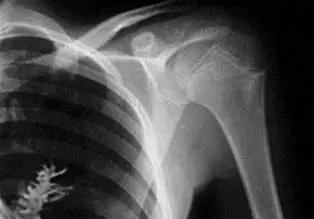

2009年,俄罗斯一男子被医生确诊癌症,可当医生打开他的胸腔,切下肺部患癌组织的时候,惊讶的发现,他得的并不是癌症,那团黑影竟然是一颗树...... 麻烦看官老爷们右上角点击一下“关注”,既方便您进行讨论和分享,又能给您带来不一样的参与感,感谢您的支持! 2009年的俄罗斯,一则新闻几乎颠覆了人们对医学的理解,那一年,在乌拉尔地区的伊热夫斯克市,一个叫阿尔乔姆·西多尔金的28岁男子,被医生诊断为肺癌中晚期。 胸痛、咳血、X光片上的阴影,全都指向了这个可怕的结论,医生告诉他必须立即手术,否则性命不保。 这个消息如同晴天霹雳,他没有选择告诉家人,只说自己要出差,独自背上了沉重的命运,可谁能想到,这场手术的结果,却让整个医学界都陷入了震惊。 主刀医生弗拉基米尔·卡马舍夫原以为这只是一次普通的肺癌切除,可当刀尖划开胸腔,准备切除“肿瘤”时,所有人都愣住了,那团阴影不是癌组织,而是一棵翠绿的小树苗。 五厘米长的冷杉,枝叶还带着湿润的色泽,根须竟然深深扎入肺部的血管,那一刻,手术室死一般的寂静。 医生们见过各种罕见病灶,却从未想象过一棵树能在人体里生长,根系刺穿毛细血管,正是这株树苗让西多尔金长期咳血。 种子如何能在肺里生根?专家们给出的解释是,他或许在林间散步时吸入了一颗冷杉的种子,那是一种生命力极其顽强的树木,种子轻如尘埃,随风飘荡。 进入人体后,肺部湿润温热,富含氧气和养分,为发芽提供了环境,尽管缺乏阳光,种子依旧在黑暗中利用自身储备发芽,顽强地长出枝叶,医生小心翼翼地将树苗摘除,清理残留组织,才保住了他的性命。 然而这件离奇的事件在科学界掀起了轩然大波,植物学家指出,冷杉这种寒带植物在人体温度下难以存活,光合作用在黑暗的胸腔里几乎不可能完成。 医学专家也质疑,五厘米的树苗生长需要时间和能量,肺部环境并不具备这样的条件,有人怀疑这是媒体的夸大报道,因为最早爆出消息的正是以玩笑新闻闻名的俄罗斯《真理报》,时间又刚好接近旧历愚人节。 更有学者指出,当时流传的X光照片看起来不像成年人的骨骼,而更像儿童的影像。 可另一方面,医学史上确实存在一些诡异的案例,有人曾因误吸豌豆,导致其在支气管内发芽;有人体内异物滋生出霉菌球,密度和形状酷似肿瘤,也会造成严重出血。 西多尔金的症状与此类情况有相似之处:胸口疼痛、咳血、影像异常,如果说种子只是短暂发芽,而非真正长成完整的树木,那么也并非全无可能。 这场争论并没有随着手术结束而平息,加拿大的生态学家、英国的皇家植物园专家、欧洲林业研究人员纷纷发声,质疑与惊叹交织在一起。 有人把这看作医学史上最奇特的案例,有人则认为是媒体操作下的“都市传说”,无论如何,这一新闻迅速在全球流传,成为当年点击量最高的奇闻之一。 对于西多尔金本人来说,这场手术是一场劫后余生,他术后恢复顺利,肺功能检测正常,很快重返工厂继续工作,他没有接受大规模采访,只在少数媒体报道中留下模糊的身影。 那棵被摘除的小树苗,成为医学会议和媒体报道里的唯一证物,有人说它被保存为研究标本,也有人怀疑它不过是一段被加工过的树枝,真相至今未有明确定论。 可不管是真是假,这段经历都成为人们探讨生命奥秘的一面镜子,一个普通工人,因为一次突如其来的身体异常,被推上全球新闻的舞台。 医学专家们争论不休,民众则在好奇与震惊中,重新思考身体的脆弱与自然的力量,人类总以为科学能解释一切,但这件事提醒我们,未知仍然广阔,哪怕是一颗微小的种子,都可能成为撼动认知的谜团。 在这场故事中,有恐惧,有质疑,也有幸运,西多尔金没死于癌症,反而因这场意外继续了平凡的人生。 他像往常一样上班、回家,和妻子过着朴实的日子,只是当人们提起那棵在他体内长出的树,总觉得这背后藏着一种隐喻,生命就像大地,脆弱却又强大,有时一颗尘埃,就能改变整个命运的走向。 或许那棵冷杉的真假已不再重要,重要的是,它提醒人类:科学不是终点,自然也并未展现出所有的面孔,真正的奇迹,往往发生在最意想不到的地方。 对此大家有什么想说的呢?欢迎在评论区留言讨论,说出您的想法! 信源:环球时报——俄罗斯一男子肺里长出冷杉树(图)